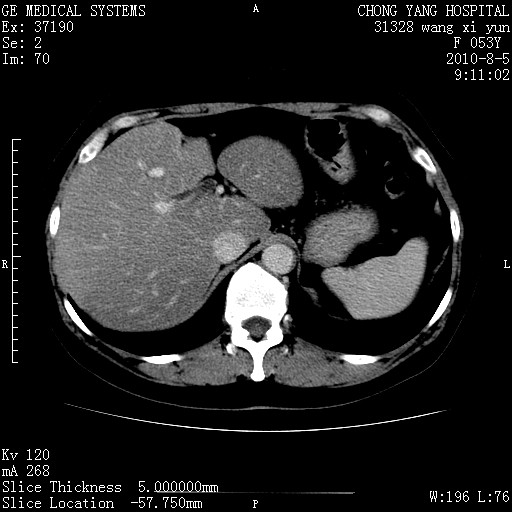

标题: CT28214:F41Y 血尿二十天,建议盆腔平扫加增强。

1)考虑肝左叶胆管细胞癌。2)脂肪肝。